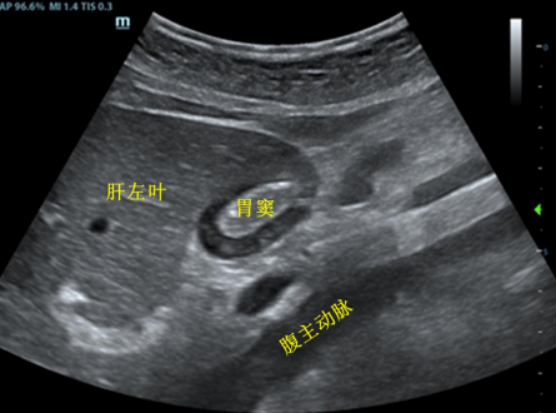

4. 标准图像应以探查到肝左叶和腹主动脉夹角处的环状结构(置于屏幕中心线), 深度以显示腹主动脉最浅深度为准(2)

图片

2  胃窦短轴标准切面超声图像